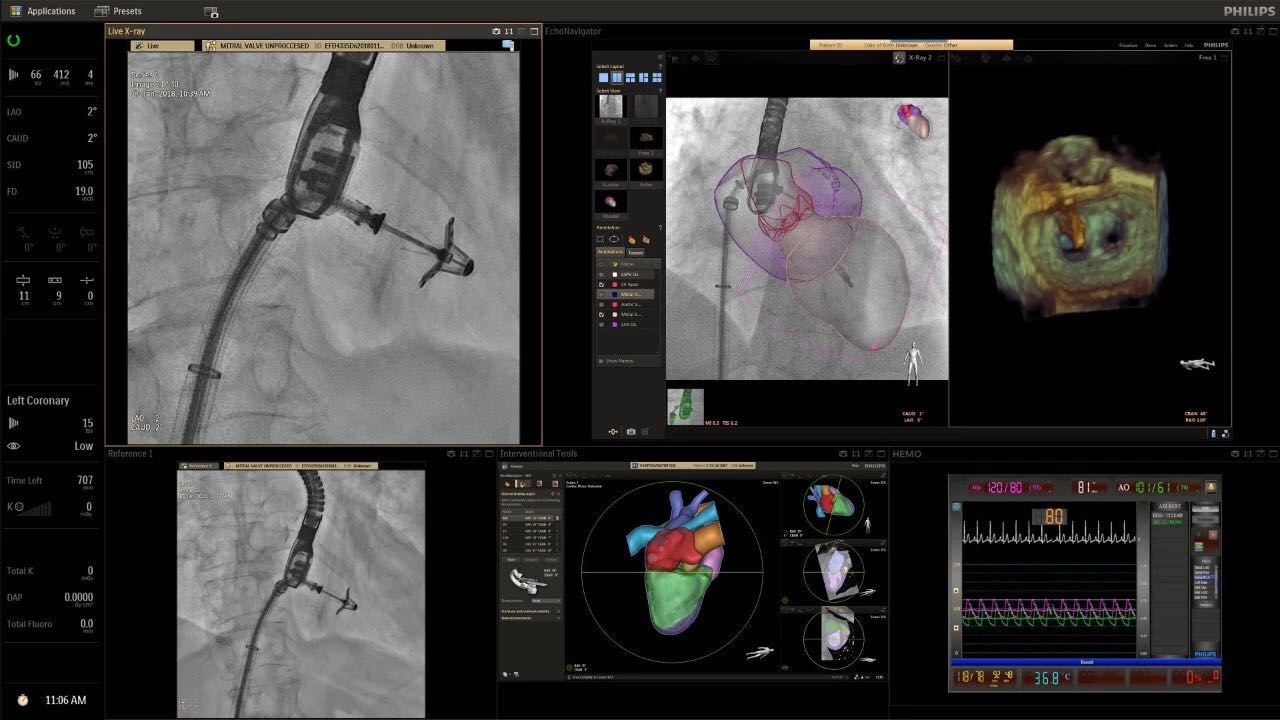

在日益復(fù)雜的干預(yù)期間,臨床醫(yī)生需要快速、輕松地可視化關(guān)鍵解剖結(jié)構(gòu)并確定手術(shù)過程中患者的變化。2019年1月17日,飛利浦宣布推出采用FlexArm的Azurion 7 C20,旨在提高圖像引導(dǎo)程序的定位靈活性。

帶有FlexArm的Azurion 7 C20 包含一系列創(chuàng)新技術(shù),使臨床醫(yī)生可以更輕松地在整個(gè)患者身上進(jìn)行二維和三維成像。當(dāng)臨床醫(yī)生移動(dòng)系統(tǒng)時(shí),圖像光束自動(dòng)保持與患者的對準(zhǔn),允許更一致的可視化并使他們能夠?qū)⒆⒁饬性谥委熒稀?/span>

“憑借FlexArm,飛利浦的工程師已經(jīng)克服了幾乎不可能的幾何和機(jī)械障礙,使臨床醫(yī)生能夠在圖像引導(dǎo)治療方面實(shí)現(xiàn)臨床卓越,”邁阿密心臟與血管研究所創(chuàng)始人兼首席醫(yī)療主管Barry T. Katzen博士說?!癋lexArm使我們能夠大大優(yōu)化患者周圍的程序,我們可以最佳地了解患者體內(nèi)的情況,而不會妨礙所有在桌面上工作的臨床醫(yī)生。結(jié)果是一項(xiàng)不僅具有臨床重要性,而且使用起來非常簡單直觀的創(chuàng)新。這是復(fù)雜手術(shù)過程中的一個(gè)關(guān)鍵因素。”

(FlexArm C型臂可以沿著工作臺的兩側(cè)提供偏心成像。這允許醫(yī)生在左臂或右臂上進(jìn)行徑向進(jìn)入病例,完全或部分伸展,而無需移動(dòng)患者或樞轉(zhuǎn)桌子。X射線束與手臂保持對齊,以促進(jìn)其整個(gè)長度的平滑導(dǎo)航,而無需進(jìn)行持續(xù)調(diào)整。)

飛利浦表示,采用FlexArm設(shè)計(jì)的Azurion 7 C20可提供卓越的靈活性和直觀的控制。該系統(tǒng)由智能運(yùn)動(dòng)引擎驅(qū)動(dòng),可在八個(gè)不同的軸上移動(dòng),所有這些軸均由其單個(gè)“Axsys”控制器控制。臨床醫(yī)生的模擬測試表明,該系統(tǒng)有可能顯著減少患者,工作人員和設(shè)備的重新定位,從而改善微創(chuàng)手術(shù)的可及性,包括通過患者手腕進(jìn)入身體的手術(shù)(橈動(dòng)脈入路),并降低患者的風(fēng)險(xiǎn)。無意中拔出電線和管子,以及節(jié)省大量時(shí)間。該系統(tǒng)非常適合混合手術(shù)室(OR),可滿足一個(gè)房間內(nèi)的多種專業(yè)需求,例如手術(shù)和血管內(nèi)手術(shù)的組合。

FlexArm在不少于8軸的情況下旋轉(zhuǎn),從而創(chuàng)建幾乎無限的靈活性來執(zhí)行成像,從頭部到腳部在左側(cè)和右側(cè)進(jìn)行2D和3D可視化。圖像光束保持與患者對齊,允許在旋轉(zhuǎn)或角度期間更好地可視化解剖結(jié)構(gòu)。使用Axsys運(yùn)動(dòng)控制系統(tǒng)輕松操作支架。